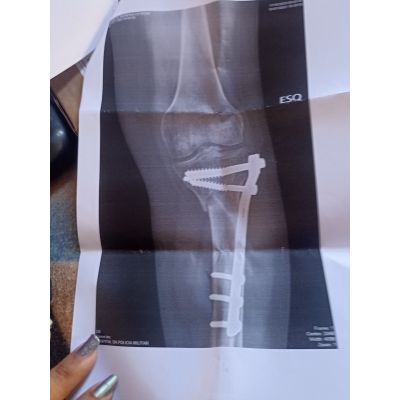

Sua radiografia mostra uma fratura complexa.

Vamos analisar as imagens:

A placa metálica e os parafusos estão bem posicionados,

Não há sinal de soltura ou quebra do material metálico. Isso é bom.

A linha da fratura parece parcialmente consolidada, mas ainda com áreas que sugerem cicatrização óssea incompleta. isso pode justificar a dor e a dificuldade de apoiar o peso.

Em fraturas desse tipo o tempo médio para andar sem apoio total varia de 4 a 8 meses. Então, ainda estar com dor e muletas após 5 meses não é anormal, mas também não é o ideal. Isso merece reavaliação com ortopedista para ver se o osso já consolidou totalmente ou se há atraso (pseudoartrose).